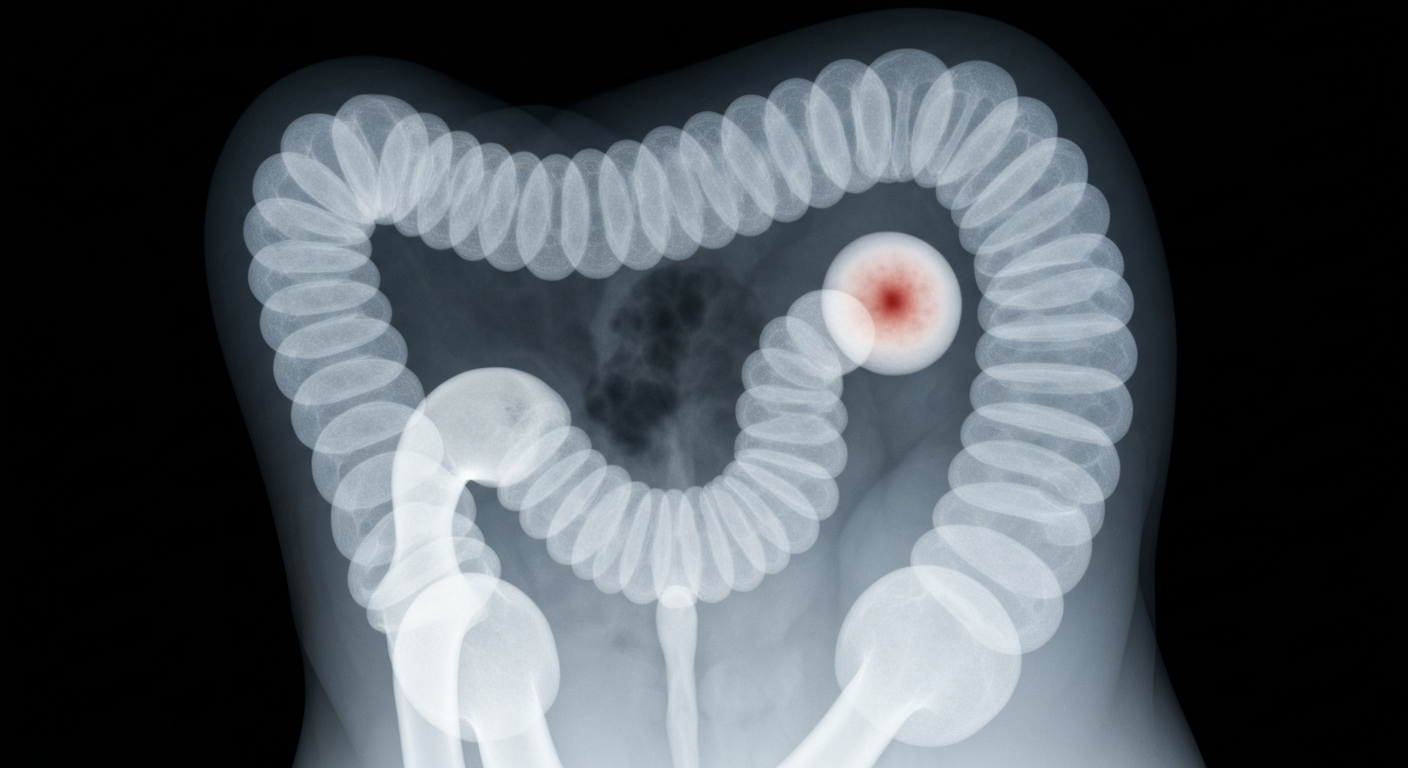

An X-ray view exposes the internal structures of the colon, highlighting the need for vigilance and early screening to detect cancer before it advances.NYC TodayA 22-year-old recent college graduate was diagnosed with a large colon tumor after experiencing unexplained stomach pain for about a year. Dr. Marc Greenwald, who treated the patient, says colon cancer cases are increasing in younger adults, even those without a family history. He emphasizes the importance of seeking medical attention for any new or persistent symptoms, as early-onset colon cancers may not cause obvious signs until the disease has advanced.

Dr. Greenwald's 22-year-old patient had been experiencing intermittent stomach pain for about a year, which she initially attributed to stress. When the pain became severe, scans revealed a large tumor nearly blocking her colon. Despite having no family history of colon cancer, the patient was diagnosed with the disease. Greenwald says he's seeing more young colon cancer patients at his hospital, as the condition becomes less rare in people under 45. Common symptoms include abdominal pain, bloating, fatigue, changes in bathroom habits, and rectal bleeding, though early-onset cases may have subtle or no symptoms until the cancer has progressed.

- Scans found the patient had a large tumor nearly blocking her colon.